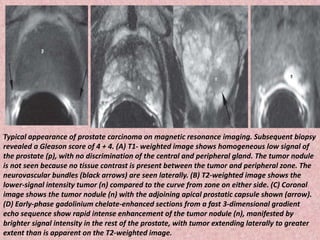

Typical appearance of prostate carcinoma on magnetic resonance imaging. Subsequent biopsy

revealed a Gleason score of 4 + 4. (A) T1- weighted image shows homogeneous low signal of

the prostate (p), with no discrimination of the central and peripheral gland. The tumor nodule

is not seen because no tissue contrast is present between the tumor and peripheral zone. The

neurovascular bundles (black arrows) are seen laterally. (B) T2-weighted image shows the

lower-signal intensity tumor (n) compared to the curve from zone on either side. (C) Coronal

image shows the tumor nodule (n) with the adjoining apical prostatic capsule shown (arrow).

(D) Early-phase gadolinium chelate-enhanced sections from a fast 3-dimensional gradient

echo sequence show rapid intense enhancement of the tumor nodule (n), manifested by

brighter signal intensity in the rest of the prostate, with tumor extending laterally to greater

extent than is apparent on the T2-weighted image.